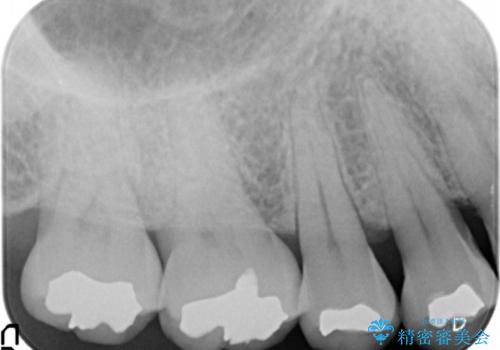

- 銀歯で詰めたところが引っ掛かるようになり舌で触ると気になる、再治療を希望され来院されました。

銀歯の劣化が見られたので化学的に安定し、長期的な予後の見込めるゴールドインレーを用いて再修復することとしました。